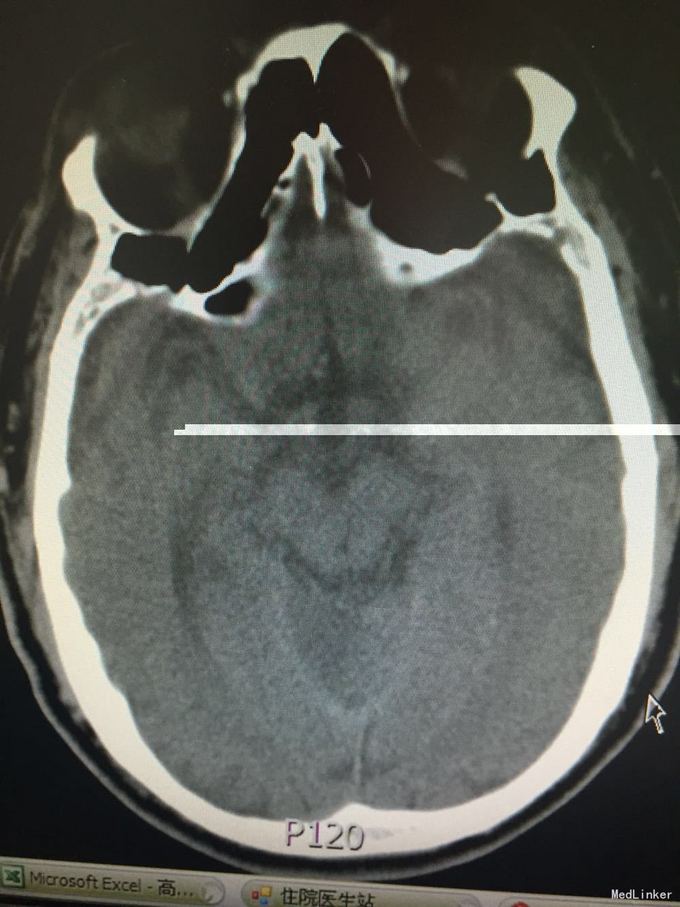

患者因突发意识不清3小时入院。既往脑梗死、高血压、糖尿病史,控制不佳。该患者于入院前3小时无明显诱因在工作中突发意识不清,起病时呼唤能回答,但口齿不清,伴右侧肢体无力,不能持物及行走,伴头痛,呕吐,呕吐物为胃内容物,测血压大于200mmHg,意识障碍快速进展加重,成昏睡状态,由120到我院,查头CT示:多发脑梗死。

T:36.0 脉搏 96 呼吸18 血压200/100,浅昏迷,双侧瞳孔等大同圆,对光反射存在,双眼右侧凝视,双眼球浮动,鼻唇沟对称,疼痛刺激后左侧肢体可正常活动,右侧肢体活动差,右侧肌张力减低,腱反射对称,右下肢病理征(+),